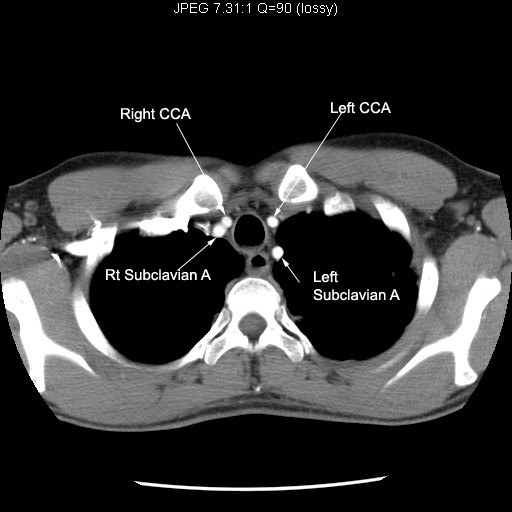

Ct Scan Chest Anatomy Images

CT Scan Tips & Protocols CT upper chest anatomy How To Read Chest Ct Scan just as playing a violin is a complex interplay of bowing, finger placement, and the mind, reading a chest ct is an interplay of visual. to read a ct scan, start by noting the shades of white, gray, and black. understand chest ct (computed tomography) scans with this clear explanation from dr. Normal ct of the chest. How To Read Chest Ct Scan.